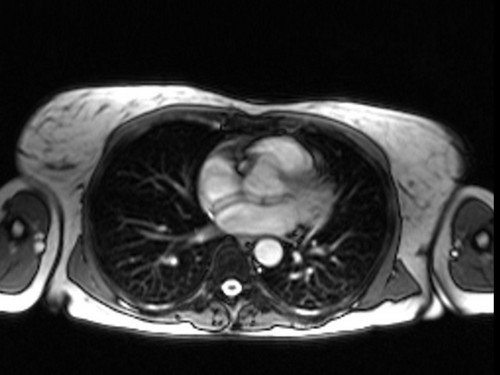

heart mri localizer 1 - MRI